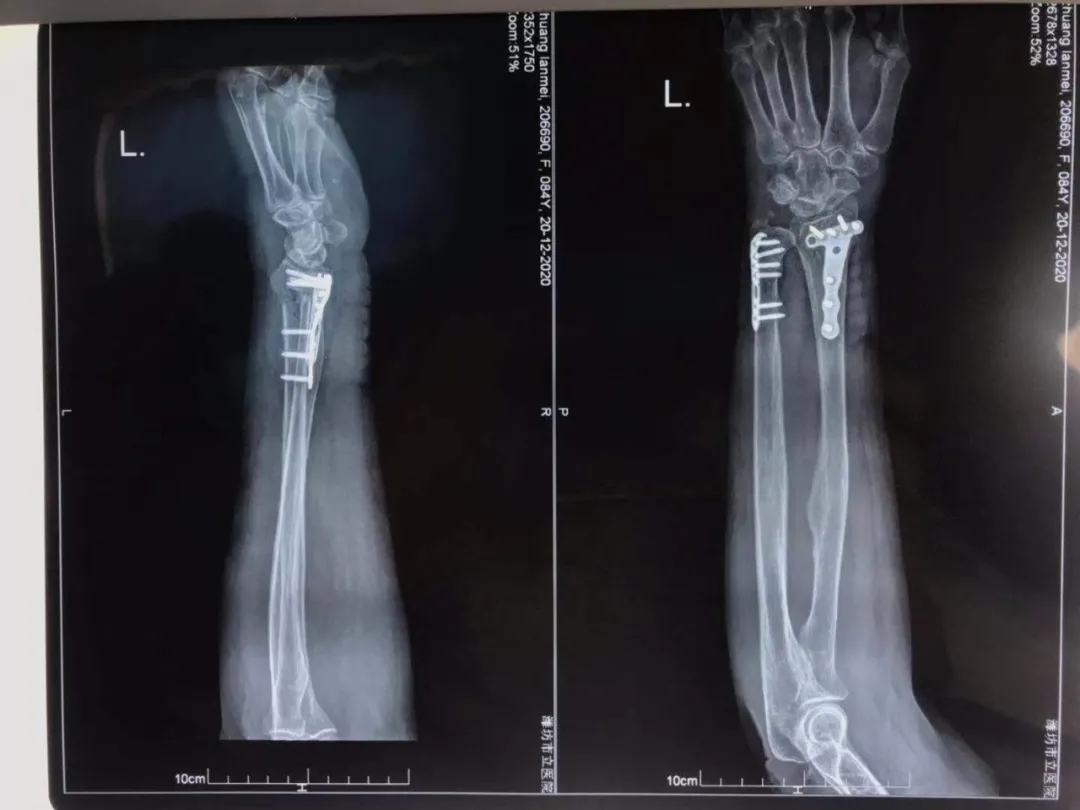

李奶奶畢竟已是高齡,身體機(jī)能處于衰退狀態(tài), 一次骨折就是一場生死考驗(yàn)。經(jīng)過與李奶奶本人及家屬充分溝通后,創(chuàng)傷外科孫守全主任團(tuán)隊(duì)分別于12月19日、21日行尺橈骨遠(yuǎn)端骨折切開復(fù)位內(nèi)固定術(shù)及胸9椎體壓縮性骨折椎體成形術(shù),手術(shù)順利,術(shù)后病情穩(wěn)定。

患者左尺橈骨骨折術(shù)后